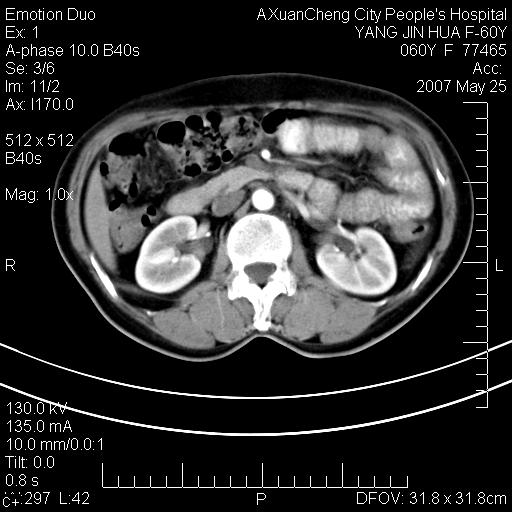

这个病理增强扫描之前,我们是考虑是血管瘤,可是现在增强后一点强化都没有,还能考虑是血管瘤吗

其内可见斑点状静脉石,血管瘤有时就不增强化,还是血管瘤。

1、病灶内有小点状钙化,静脉石?这可是血管瘤诊断的重要征象

2、病灶内有脂肪组织增生,血管瘤有此特点

还是考虑皮下血管瘤,强化不明显可能跟大量血栓形成有关,好多战友考虑血管平滑肌脂肪瘤,血管平滑肌脂肪瘤的血管就不强化么?只要有血管就都应该强化。